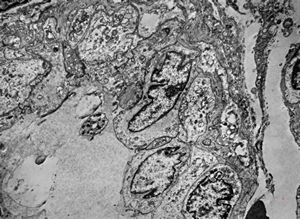

brain vessel - CADASIL - arrows:granular osmiophilic material (GOM)between basement membranes

brain vessel - CADASIL - arrow:granular osmiophilic material (GOM)in basement membrane